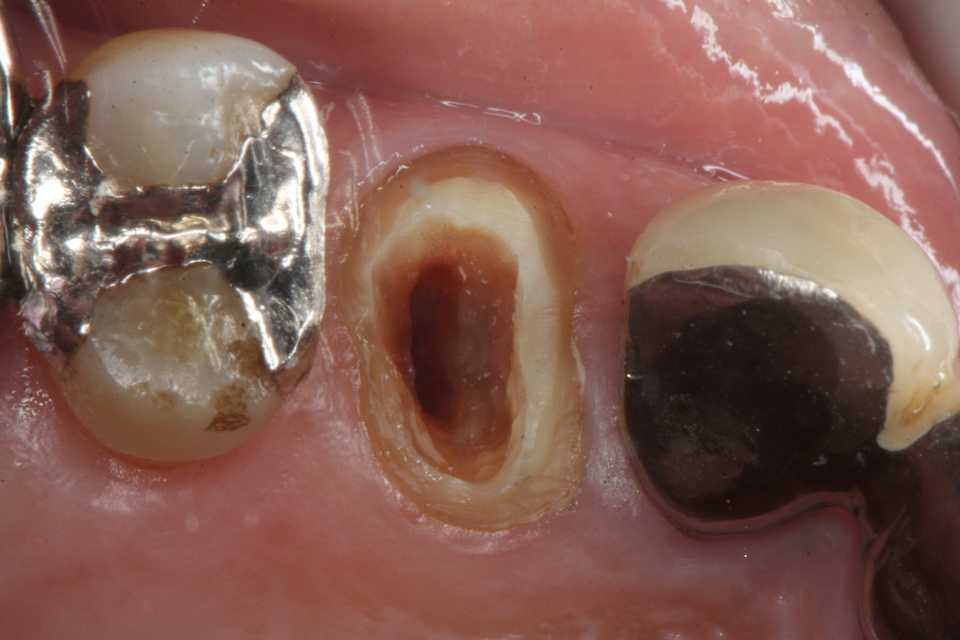

残根上のCR8 2025.10.28